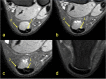

The aim of the study was to check if the subtendons of the Achilles tendon can be identified in vivo on MRI in the midportion of the tendon. The relation of the plantaris tendon to the Achilles tendon was also examined. A retrospective study of 200 MRI of ankle joints including the Achilles tendon was conducted. Statistical analysis of the correlation between the possibility of identifying the subtendons and the side, gender, presence of the central soleus tendon and plantaris tendon variation was performed. The inter-observer agreement between two reviewers in their evaluation of the subtendons was assessed using kappa statistics. The subtendon from the lateral head of the gastrocnemius muscle was identified in 65% (k = 0.63) and was located in the anterior part of the Achilles tendon. The subtendon from the soleus muscle was recognized in 12% (k = 0.75) comprising anterior part of the tendon. In 6% the subtendon from the medial head of the gastrocnemius muscle was identified (k = 0.58). The central soleus tendon was identified in 85% of cases. Statistical analysis shows the weak correlation of the presence of the central soleus tendon and the possibility of identifying the subtendon from the soleus muscle. The plantaris tendon was directly related to the insertion of the Achilles tendon in 42.5%. Identification of the subtendons of the Achilles tendon on MRI is challenging, and most often it is only possible to find the subtendon of the lateral head of the gastrocnemius muscle.